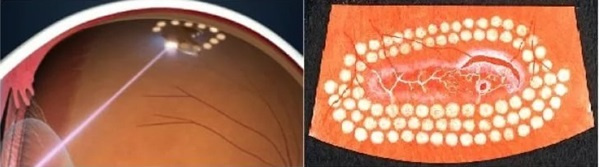

The goal of this treatment is to prevent retinal detachment.

这种治疗的目的是防止视网膜脱离。

Perform preventive barrier coagulation of the retina in the field of dystrophic changes or border laser coagulation around an existing gap. An impact on the retina along the edge of a dystrophic focus or rupture is performed, resulting in a “gluing” of the retina to the underlying eye shells at the points of exposure to laser radiation. Let me remind you that we are talking about those areas of the retina with which we «do not see», therefore after this procedure and the narrowing of the pupil, the vision is completely restored to the original.

在营养不良变化领域或在现有间隙周围进行边界激光凝结时,对视网膜进行预防性屏障凝结。 沿着营养不良性焦点或破裂的边缘对视网膜产生冲击,导致视网膜在暴露于激光辐射的点处“粘合”到下面的眼球。 让我提醒您,我们正在谈论的是我们“看不见”的视网膜区域,因此,在此过程和瞳Kong变窄之后,视力已完全恢复到原始状态。

The procedure is performed with a Goldman contact lens on the eye. This prevents involuntary eye movements and allows you to accurately focus the laser beam on the problem area.

该过程在眼睛上戴高盛隐形眼镜进行。 这样可以防止眼睛不随意移动,并使您可以将激光束准确聚焦在问题区域上。

The patient senses the laser action as flashes of bright light. As a rule, they do not cause any discomfort, but sometimes there may be a slight tingling, dizziness, or even nausea. The operation takes place in a sitting position. The eye itself is securely fixed, and the beam on a healthy retina is excluded.

病人感觉到激光在闪烁着明亮的闪光。 通常,它们不会引起任何不适,但有时可能会出现轻微的刺痛,头晕甚至恶心。 该操作在坐姿下进行。 眼睛本身固定牢固,并且排除了健康视网膜上的光束。

Laser coagulation is performed on an outpatient basis and is well tolerated by patients. It is necessary to take into account that the process of formation of adhesions takes some time, therefore, after laser coagulation is carried out, it is recommended to avoid large physical exertion, such as parachute jumping, weight lifting, etc. within 10-14 days. Otherwise, you can lead a normal life and drip 3-4 times a day preventive drops.